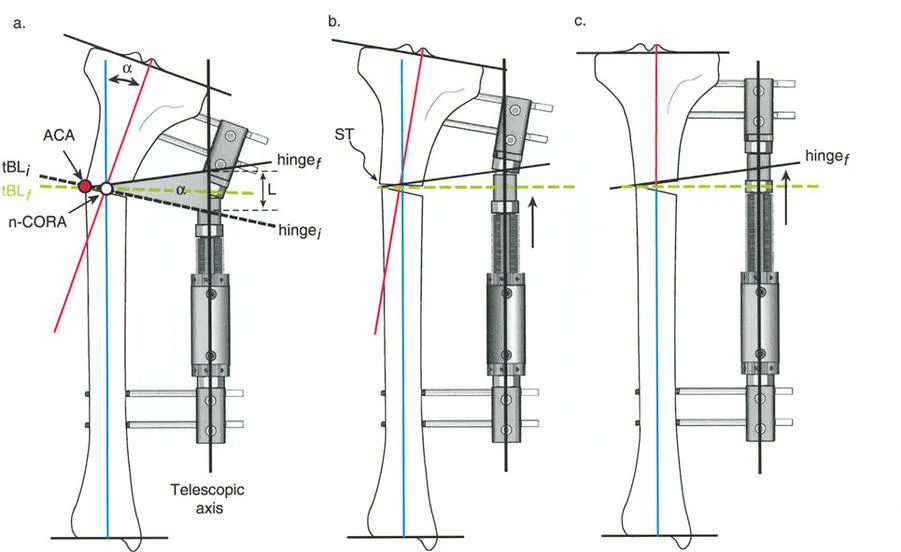

المفصلات القريبة من المفصل وقواعد قطع العظم (Osteotomy Rules)

عند التعامل مع التشوهات الواقعة بالقرب من خط المفصل - مثل التقوس الشديد في الجزء العلوي من الساق (مرض بلونت) أو التشوه الفحجي في الجزء السفلي من عظم الفخذ - يصبح وضع الجهاز مقيدًا هندسيًا. إن المتطلبات البيولوجية للحفاظ على كبسولة المفصل، وتجنب وضع الأسلاك داخل المفصل، ومنع التهاب المفاصل القيحي، غالبًا ما تجبر الجراح على وضع الحلقة المرجعية على مستوى مختلف تمامًا عن مركز دوران الانحراف (CORA) الفعلي.

تحدي مركز دوران الانحراف (CORA) القريب من المفصل

لمطابقة مفصلة المثبت الخارجي مع المستوى الدقيق لمركز دوران الانحراف (CORA)، يجب غالبًا بناء المفصلة فوق أو تحت مستوى الحلقة الفعلية. يُعرف هذا في مبادئ بالي باسم تجميع المفصلة القريبة من المفصل (juxta-articular hinge assembly).

إذا كان مركز دوران الانحراف (CORA) يقع بالقرب من خط المفصل، فإن وضع حلقة إليزاروف القياسية عند هذا المستوى بالضبط مستحيل دون انتهاك مساحة المفصل أو شد الهياكل الكبسولية الحيوية. لذلك، يتم تثبيت الحلقة المرجعية بالعظم الكثيف أو العظم الطويل المتاح، ويتم بناء آلية المفصلة باستخدام قضبان ملولبة، ولوحات توصيل، ودعامات. ثم يتم "إنزالها" (أو رفعها) لتتطابق تمامًا مع مركز دوران الانحراف (CORA) الهندسي الحقيقي.

قواعد بالي لقطع العظم (Osteotomy Rules) في وضع الأجهزة

فهم قواعد بالي لقطع العظم أمر لا غنى عنه لتخطيط الإطار:

- قاعدة قطع العظم 1: عندما يمر قطع العظم ومحور تصحيح الانحراف (ACA) كلاهما عبر مركز دوران الانحراف (CORA)، فإن نهايات العظم ستنحرف دون ترجمة (انزياح). يتم استعادة المحور الميكانيكي، وتظل نهايات العظم متقاربة تمامًا، مما يخلق تصحيحًا كلاسيكيًا "إسفينيًا مفتوحًا" أو "إسفينيًا مغلقًا".

- قاعدة قطع العظم 2: عندما يمر محور تصحيح الانحراف (ACA) عبر مركز دوران الانحراف (CORA)، ولكن يتم إجراء قطع العظم على مستوى مختلف (غالبًا بسبب ضعف جودة العظم عند CORA أو مشاكل في الجلد)، فإن نهايات العظم ستنحرف وتخضع لترجمة محسوبة ومقصودة لإعادة محاذاة المحور الميكانيكي.

- قاعدة قطع العظم 3: (للاكمال) عندما يمر قطع العظم عبر مركز دوران الانحراف (CORA)، ولكن يتم وضع محور تصحيح الانحراف (ACA) خارج CORA، سيتم إنشاء تشوه ترجمة جديد، وهو خطأ شائع في وضع المفصلات غير المخطط له جيدًا.

في المنشآت القريبة من المفصل، غالبًا ما نعتمد على قاعدة قطع العظم 2. نظرًا لأنه لا يمكننا قطع العظم بأمان عند خط المفصل تمامًا (مركز دوران الانحراف CORA)، فإننا نقطع العظم في مستوى أدنى في منطقة الميتافيسيس. بعد تحقيق التصحيح الزاوي عبر المفصلات (محور تصحيح الانحراف ACA)، يتم إعادة محاذاة خطوط المحور الميكانيكي بشكل مثالي، ولكن نهايات العظم في موقع قطع العظم تتحرك بالنسبة لبعضها البعض.